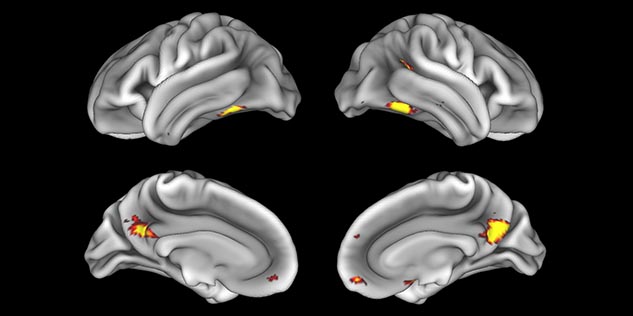

Emotional n-back task combines a test of working memory with the use of emotive (faces) and neutral (places) images. The contrast in the images is between the activity when faces are presented compared to places, showing activation in the amygdala, fusiform, and occipital face areas.

Processing based on the Human Connectome Project (HCP) pipelines. The high resolution of the fMRI data allows extraction of the cortical surface, with minimal averaging of non-cortical signal. Surface based analysis provides improved cross-subject alignment, and prevents signal contamination between adjacent sulci.

Group analysis of 88 9- and 10-year olds part of ABCD, all scanned at UVM on Philips Achieva 3.0T dStream. Scale runs from red p=0.001 to yellow p<10ˆ-5. Images provided by Dr. Watts.

Acquisition using the ABCD protocol for fMRI with TR 800 ms, TE 30 ms, flip angle 52°, 2.4 mm isotropic imaging resolution with a 216×216×144 mm3 field of view using a MultiBand acceleration factor of 6 (60 slices, no gap). Two runs of 5 minutes per subject.